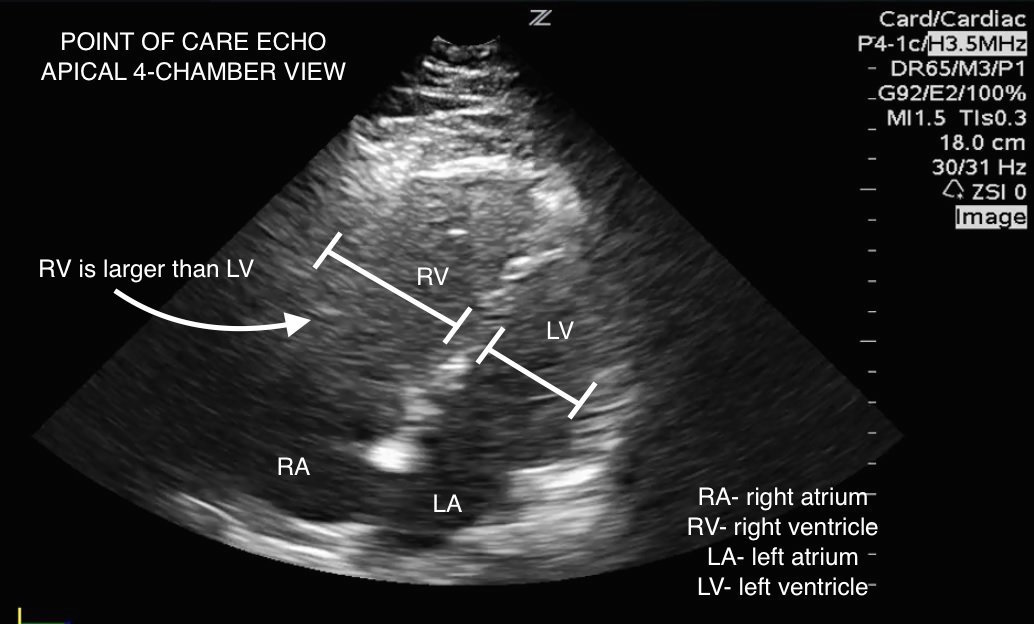

The patient has probably got a massive PE. There are several treatment options available, some more available than others depending on where you work. The RCOG suggest calling the consultant obstetrician, I would also be chatting to a respiratory consultant and getting a cardiologist to come and do an echo to look for a dilated RV (evidence of right heart strain).

(Courtesy of westjem.com)